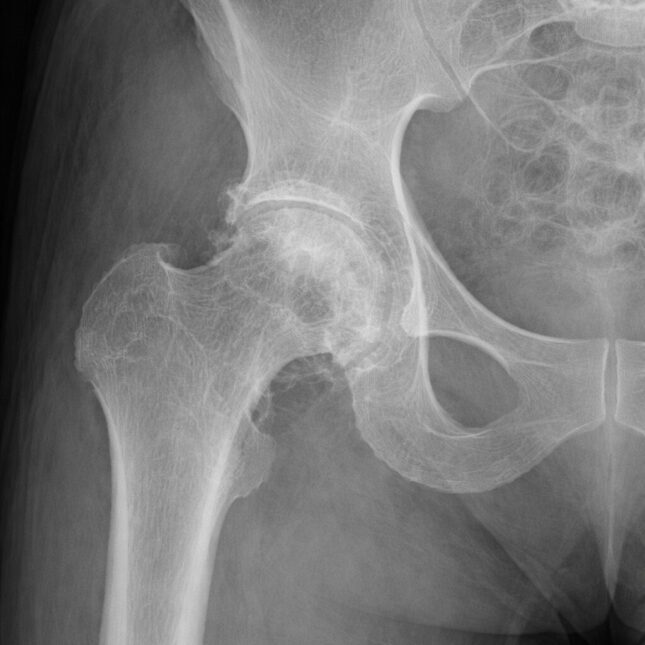

Рентгеновский снимок тазобедренного сустава с признаками остеоартрита.

Синтетический рентгеновский снимок тазобедренного сустава, созданный Микаэлем Торджманом с помощью Chat GPT.

Синтетический рентгеновский снимок тазобедренного сустава, созданный Микаэлем Торджманом с помощью ChatGPT. В новом исследовании Торджман и его коллеги проверили, могут ли рентгенологи отличить настоящие рентгеновские снимки от снимков, созданных с помощью ChatGPT. Микаэль Торджман

В исследовании, опубликованном во вторник в журнале Radiology, международная группа исследователей проверила, могут ли 17 рентгенологов отличить настоящие рентгеновские снимки от снимков, сгенерированных ChatGPT. Только 41% заметили отклонения, когда их первоначально попросили поставить диагноз пациентам на основе синтетических изображений. Даже зная, на что обращать внимание при обнаружении поддельных рентгеновских снимков, они смогли точно отличить их только в 75% случаев.

Эти изображения несложно сгенерировать: исследователи использовали простые подсказки, чтобы заставить ChatGPT выдавать рентгеновские снимки с указанным анатомическим расположением, заболеванием и уровнем шума. Но, несмотря на то, что моделям легко создавать убедительные рентгеновские снимки, они не могут надежно их обнаружить. Четыре мультимодальные модели, включая ту, которая сгенерировала изображения, точно различали дипфейки лишь в 57–85% случаев.